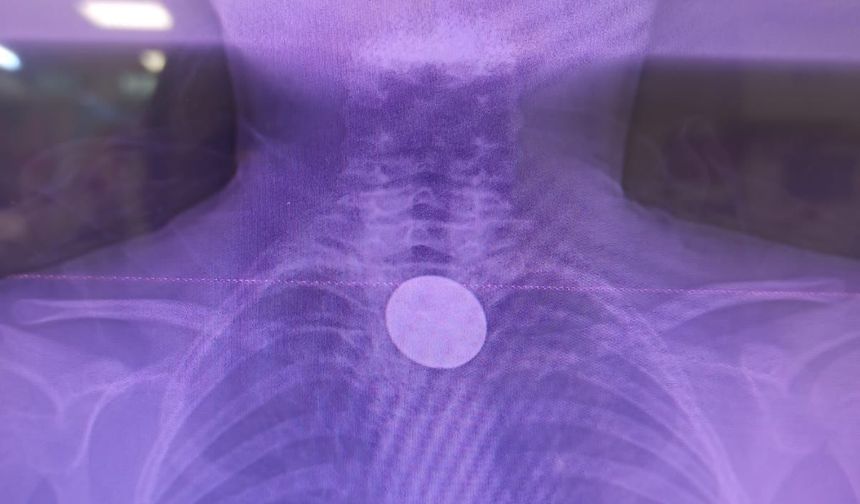

Siirt’te küçük çocuğun yuttuğu madeni para başarılı operasyonla çıkarıldı